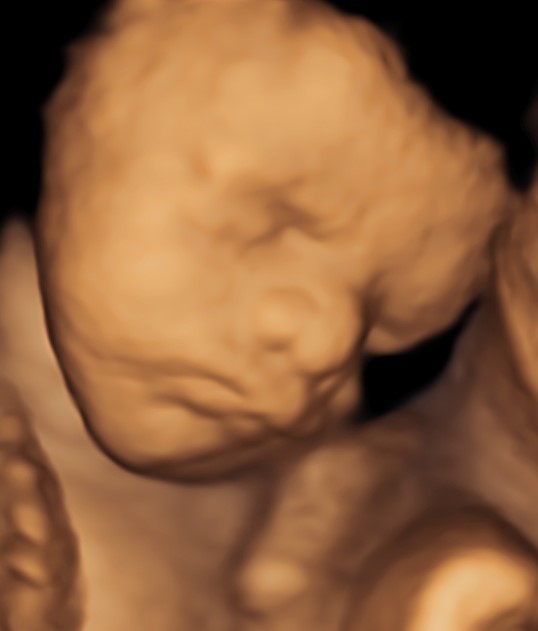

4D/5D/HD Ultrasound Gallery

Gallery